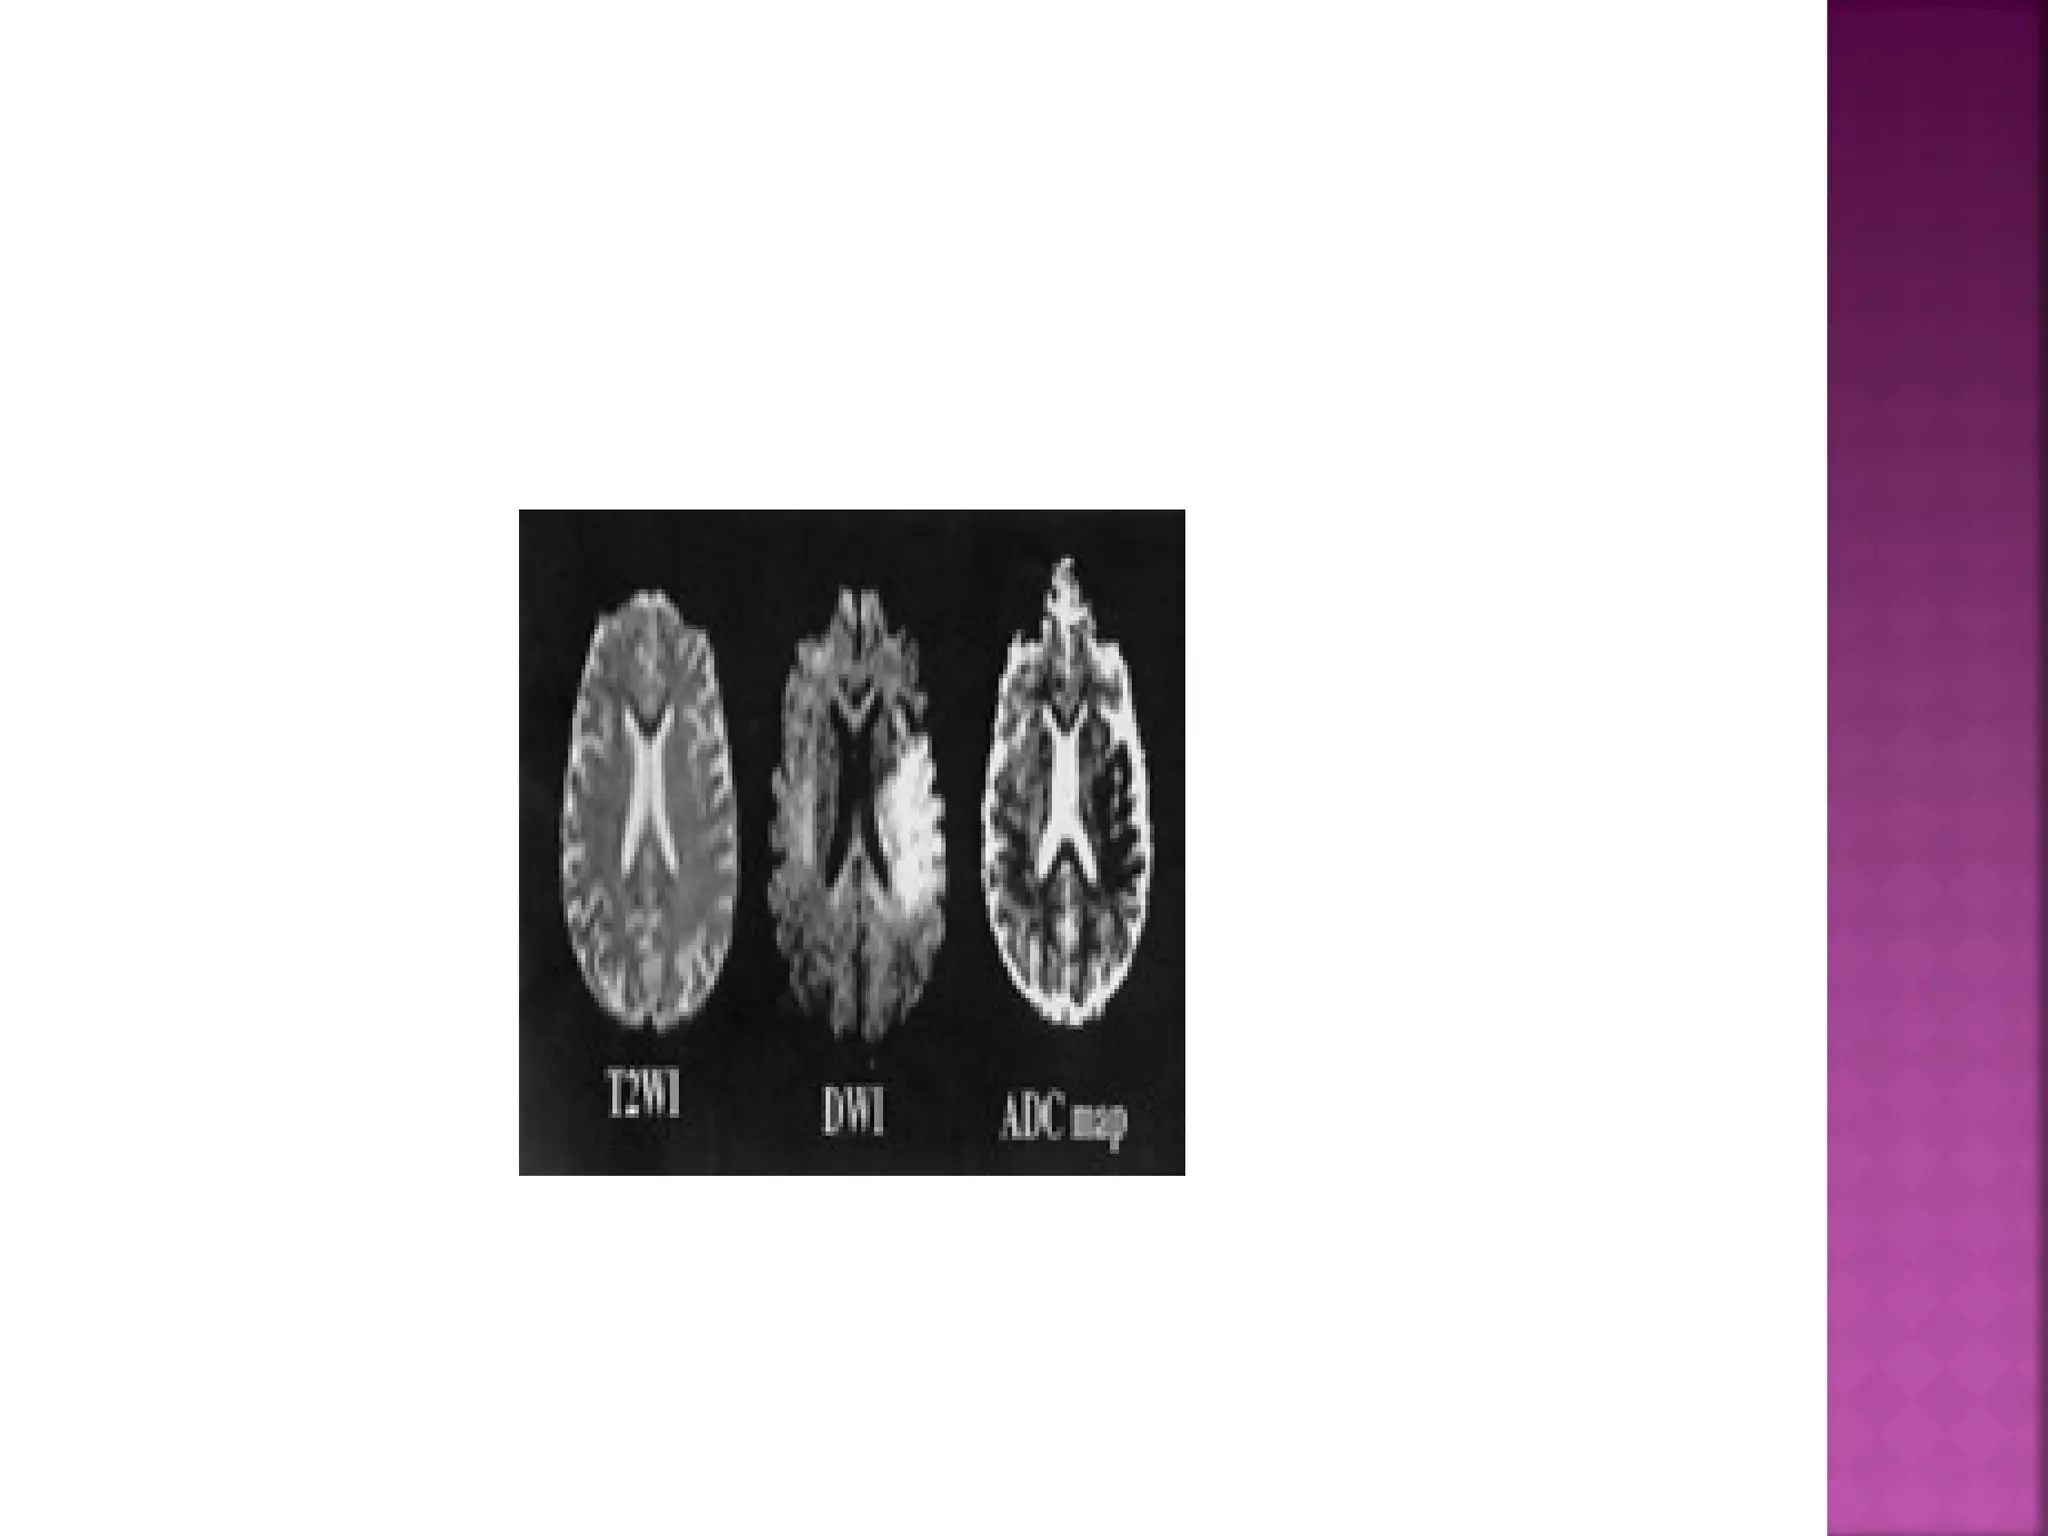

DWI is the most sensitive sequence for stroke

imaging.

DWI is sensitive to restriction of Brownian

motion of extracellular water due to

imbalance caused by cytotoxic edema.

Normally water protons have the ability to

diffuse extracellularly and loose signal.

High intensity on DWI indicates restriction of

the ability of water protons to diffuse

extracellularly.

ADC will be of low signal intensity with a

maximum at 24 hours and then will increase

in signal intensity and finally becomes bright

in the chronic stage.